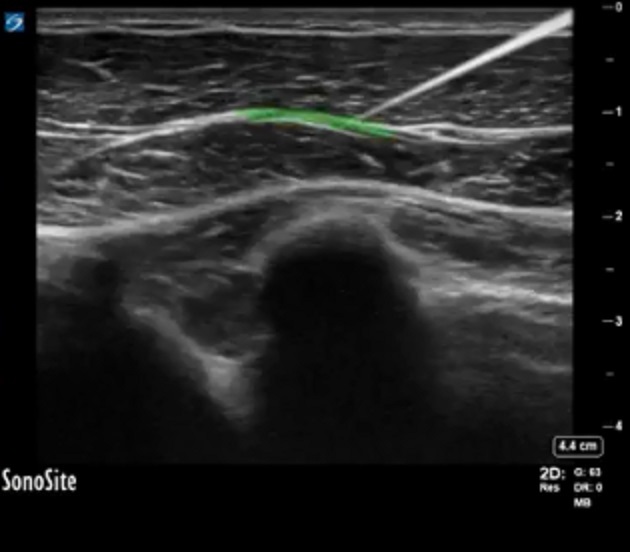

Highlighted Area: Fascia between the pectoralis major muscle and pectoralis minor muscle